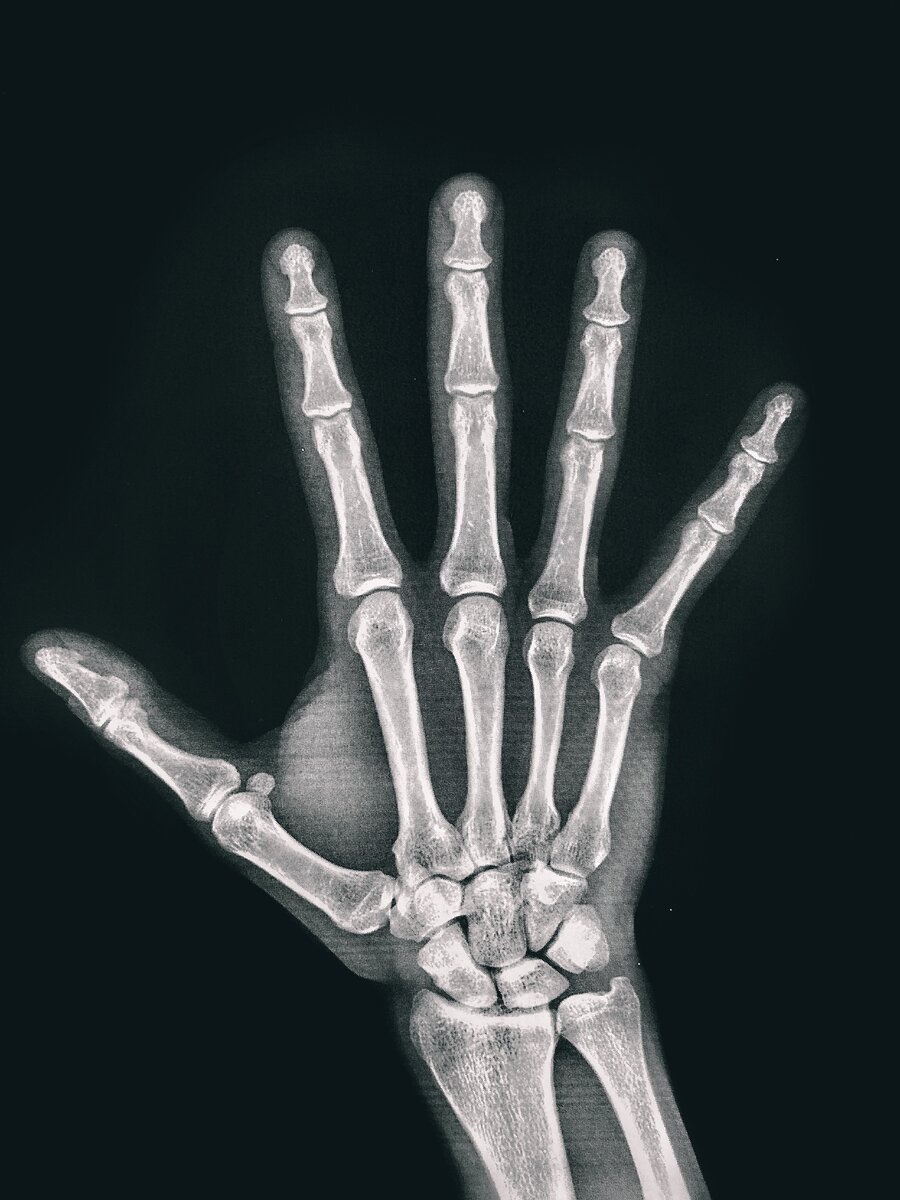

Мне руку в двух позах отщелкали,

И что без рентгена бессмысленно.